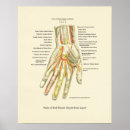

Poster interno da anatomia da mão & do pulso

Preço44,35 €

Poster interno da anatomia da mão & do pulso

Preço48,95 €

Poster interno da anatomia da mão & do pulso

Preço44,35 €

Poster interno da anatomia da mão & do pulso

Preço48,95 €

Poster interno da anatomia da mão & do pulso

Preço48,95 €

Poster de Anatomia Interna da Mão e Pulso

Preço44,35 €